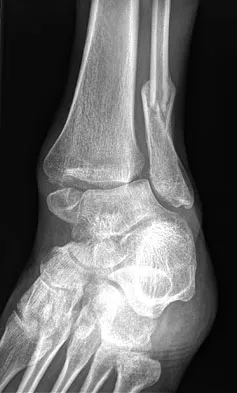

Question 67 High Yield

A 32-year-old laborer reports left ankle pain and deformity. History reveals that he sustained a left ankle fracture 2 years ago and was treated with closed reduction and casting. Radiographs are shown in Figures 25a through 25c. What is the most appropriate management?

Detailed Explanation

Corrective osteotomy of fibular malunions, with appropriate lengthening, even in the presence of early arthritis, has been shown to decrease ankle pain and increase stability. Reduction and bone grafting of the medial malleolar nonunion is also needed. There is no evidence supporting the use of intra-articular steroids or hyaluronic acid in the ankle joint. Lateral talar displacement of even 1 mm has been reproducibly shown to decrease tibiotalar contact by 40% to 42%, causing a predisposition to arthritis. Weber D, Friederich NF, Muller W: Lengthening osteotomy of the fibula for post-traumatic malunion: Indication, technique and results. Int Orthop 1998;22:149-152. Lloyd J, Elsayed S, Hariharan K, et al: Revisiting the concept of talar shift in ankle fractures. Foot Ankle Int 2006;27:793-796. Offierski CM, Graham JD, Hall JH, et al: Later revision of fibular malunion in ankle fractures. Clin Orthop Relat Res 1982;171:145-149.